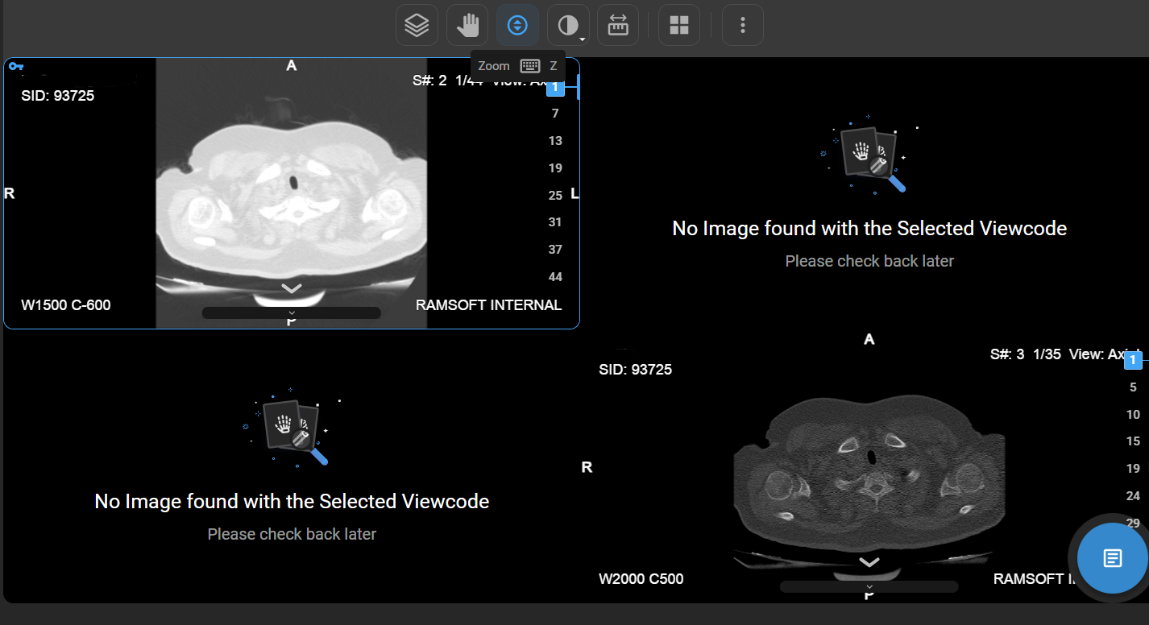

How Do I Change the Viewport Layout?

1. Open Layout Selector from the toolbar.

a. A 3×3 grid appears, with the current layout highlighted.

1. Adjust Viewports:

a. Drag to increase/decrease viewports (up to 8×8 grid per monitor).

How Do I View Multiple Images or Series in Different Layouts?

• If there are multiple images or a series of images, you can customise the display layout to enhance your viewing experience.

• Locate and click on the Change Layout icon in the image viewer toolbar at the top of the screen.

vai

• Select the desired layout format to switch between a single-frame view and a multi-frame display for comparing multiple images simultaneously.